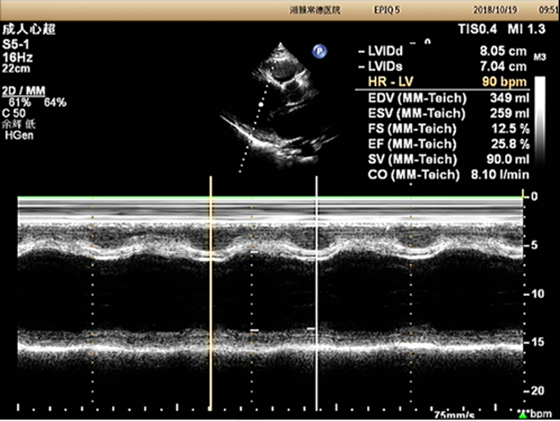

患者心脏超声检查结果